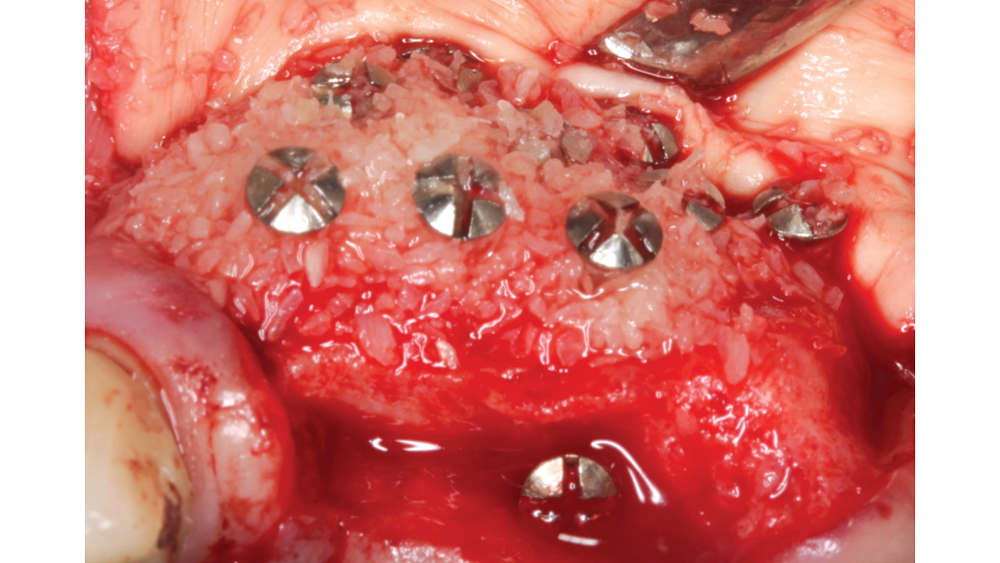

Newport Biologics™ Mineralized Cortico/Cancellous Allograft Blend (Glidewell Direct; Irvine, Calif.) possesses the optimal features of cortical and cancellous bone, with particle sizes that allow for rapid site revascularization and increased structural integrity. The cancellous bone allows for better cell migration and faster remodeling, and the cortical bone provides the space maintenance that allows the time for bone regeneration to occur. The particle size is approximately 250–1,000 microns, with a turnover rate of 4–6 months for predictable bone regeneration. Shown are various clinical GBR and lateral ridge augmentation procedures with the use of mineralized cortico/cancellous bone.

• Ideal particle form — Allografts are available in three particle forms: cortical, cancellous and cortico/cancellous. Cortical allografts are associated with an increased density and greater space maintenance properties, which allow for slower resorption. Cancellous chips are advantageous because they allow for osteoconductive scaffolding and deposition of osteoblasts while also providing faster resorption. The cortico/cancellous mixture allows for the benefits of both cancellous and cortical bone.

• Ideal particle size — The particle size of the allograft material is very important in the bone regeneration process, as a particle size that is too small (less than 125 microns) leads to fast resorption with inconsistent bone formation. A larger particle size (greater than 1,000 microns) restricts resorption and may be sequestered or result in delayed healing. Studies have shown an ideal particle size for predictable bone regeneration to be approximately 250–1,000 microns.7